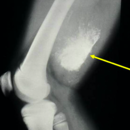

Radiographic imaging is used to help form a diagnosis. These include X-Ray, MRI, CT and Bone Scans

An example of an Mesenchymal Chondrosarcoma MRI is shown.